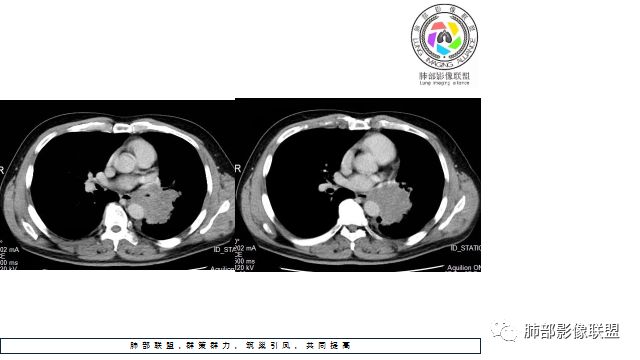

1.左下肺门区巨大肿块,支气管显示不清,轻度阻塞性炎症,没有明显肺不张,提示管腔受压狭窄可能性大于堵塞,这较少见于鳞癌。

2.病灶边缘光滑,未见明显分叶、毛刺,未见明显强化,这符合腺癌影像学特点,却符合神经内分泌癌表现。

3.病灶内密度均匀,轻到中度均匀强化,大病灶未见明显液化坏死区及空洞,不符合鳞癌而符合小细胞肺癌特点。

4.病灶内有肺动脉走形,血管局部受压,未见破坏,病灶乏血供,呈血管包埋或血管造影征;侵袭性力强及破坏力弱、血管漂浮都符合SCLC,所以鳞癌的可能性也不大。

5.左肺门块影或淋巴结肿大,竭力挤兑肺门血管结构,呈冰冻肺门;有时候SCLC可以单独呈现冰冻肺门,而没有没有冰冻纵隔。